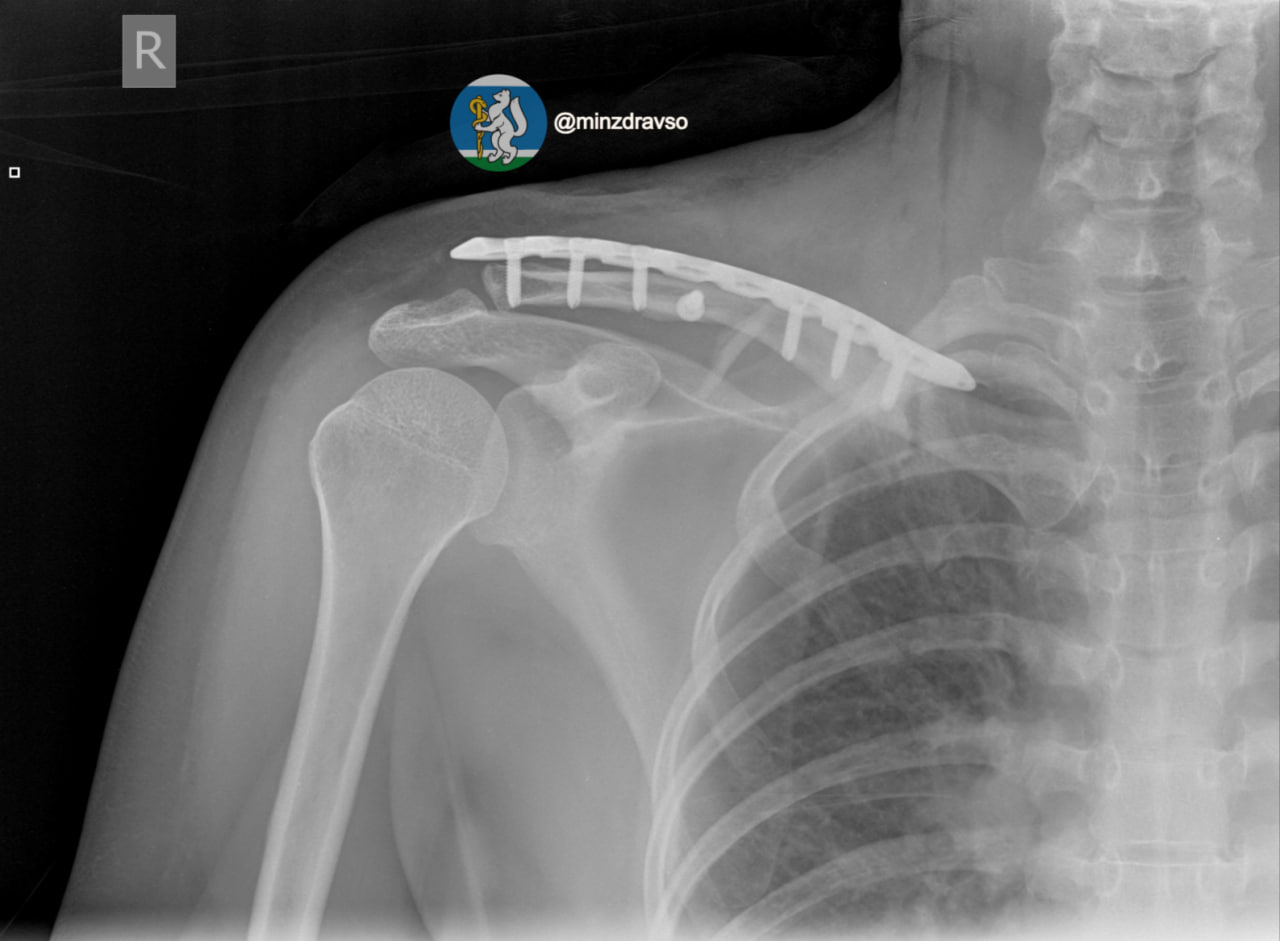

Врачи екатеринбургской травматологической больницы № 36 вернули к жизни 44-летнюю женщину после жуткой аварии, сообщает Министерство здравоохранения Свердловской области.

Пострадавшую не просто сбила машина. Автомобиль буквально переехал её.

Пациентку доставили в реанимацию с «букетом» тяжелейших травм: от серьёзных повреждений головы и челюсти до раздробленных костей таза и рёбер. Ситуация осложнялась риском огромной кровопотери.

Чтобы спасти женщину, медики буквально по кусочкам соединили обломки костей с помощью специальных аппаратов внешней фиксации.

В итоге профессионализм екатеринбургских врачей подарил женщине второй день рождения. Врачи не только спасли пациентку, но и сохранили ей возможность ходить.